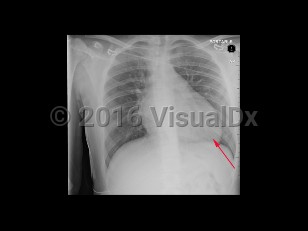

Hypertrophic cardiomyopathy

Hypertrophic cardiomyopathy is caused by an abnormality of heart muscle, usually caused by a genetic mutation of a sarcomeric protein, that results in disrupted myocardial alignment known as myocardial disarray. The result is regional hypertrophy with variable involvement of myocardium. Hypertrophy of the basal septum, adjacent to the left ventricular outflow tract (LVOT), may result in outflow obstruction.

Presenting symptoms are variable, and many patients remain asymptomatic for decades. When symptoms develop, they are often associated with LVOT obstruction and may include dyspnea, palpitations, syncope, or sudden cardiac death. HCM can be diagnosed at any stage of life. It is the most common cause of sudden cardiac death in young athletes.